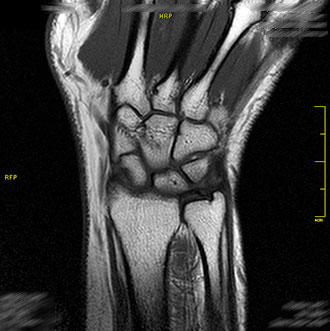

Die MRT des Handgelenks ermöglicht eine sehr genaue Darstellung von Knochenveränderungen, Sehnenverletzungen und Verletzungen des Diskus triangularis (TFCC).

Auch Arthrose oder entzündliche Erkrankungen können exakt beurteilt werden.

Im Kernspin Zentrum Köln wird diese Untersuchung häufig bei chronischen Handgelenkschmerzen oder nach Stürzen eingesetzt.